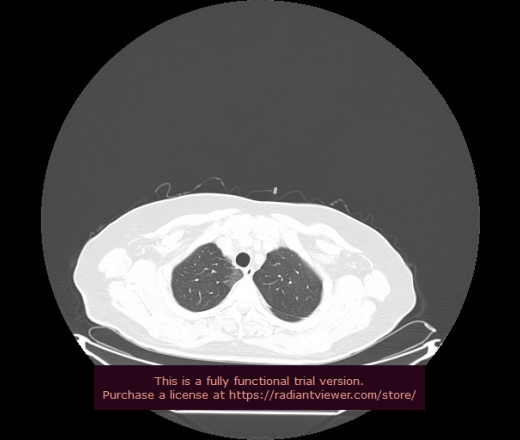

Уважаемые коллеги, если имеется интерес, сможете ли Вы спрогнозировать дальнейшее +-одинаковое течение процесса у 4 данных разных пациентов? Зацепиться где-то можно очень просто, где-то нельзя.